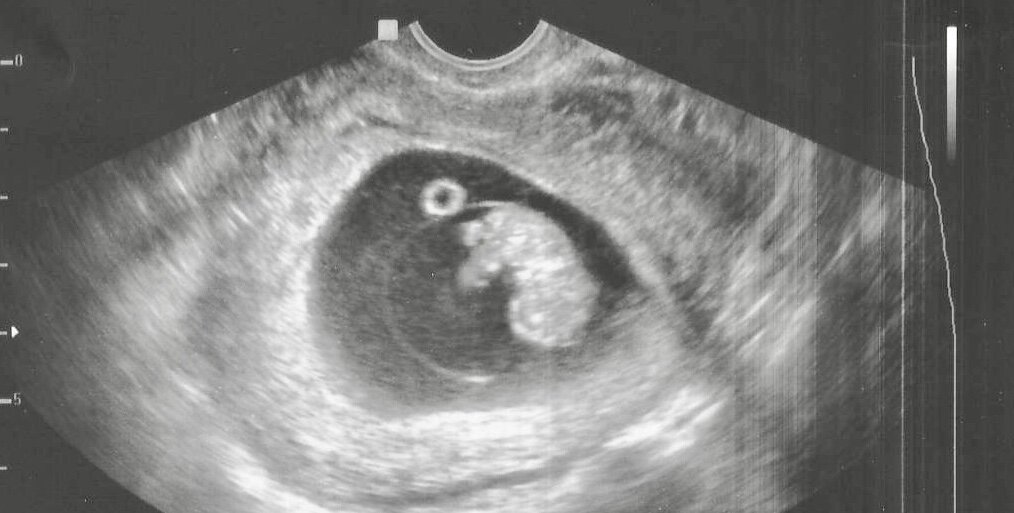

Я приступила к выполнению УЗИ. На мониторе отчетливо визуализировался один живой плод. Срок беременности, учитывая копчико-теменной размер (КТР), составлял 8-9 недель беременности.

Матка женщины была увеличена соответственно сроку, развитие плода было без особенностей.

УЗИ при беременности раннего срока

Я рассказала и показала супругам, как сформирован малыш, его двигательную активность, объяснила, что сердцебиение ритмичное, указав на расположение сердца, включила режим доплера, чтобы супруги могли послушать, как бьется сердца малыша.

Также сообщила, что частота сердечных сокращений плода в норме и отсутствует угроза прерывания беременности.